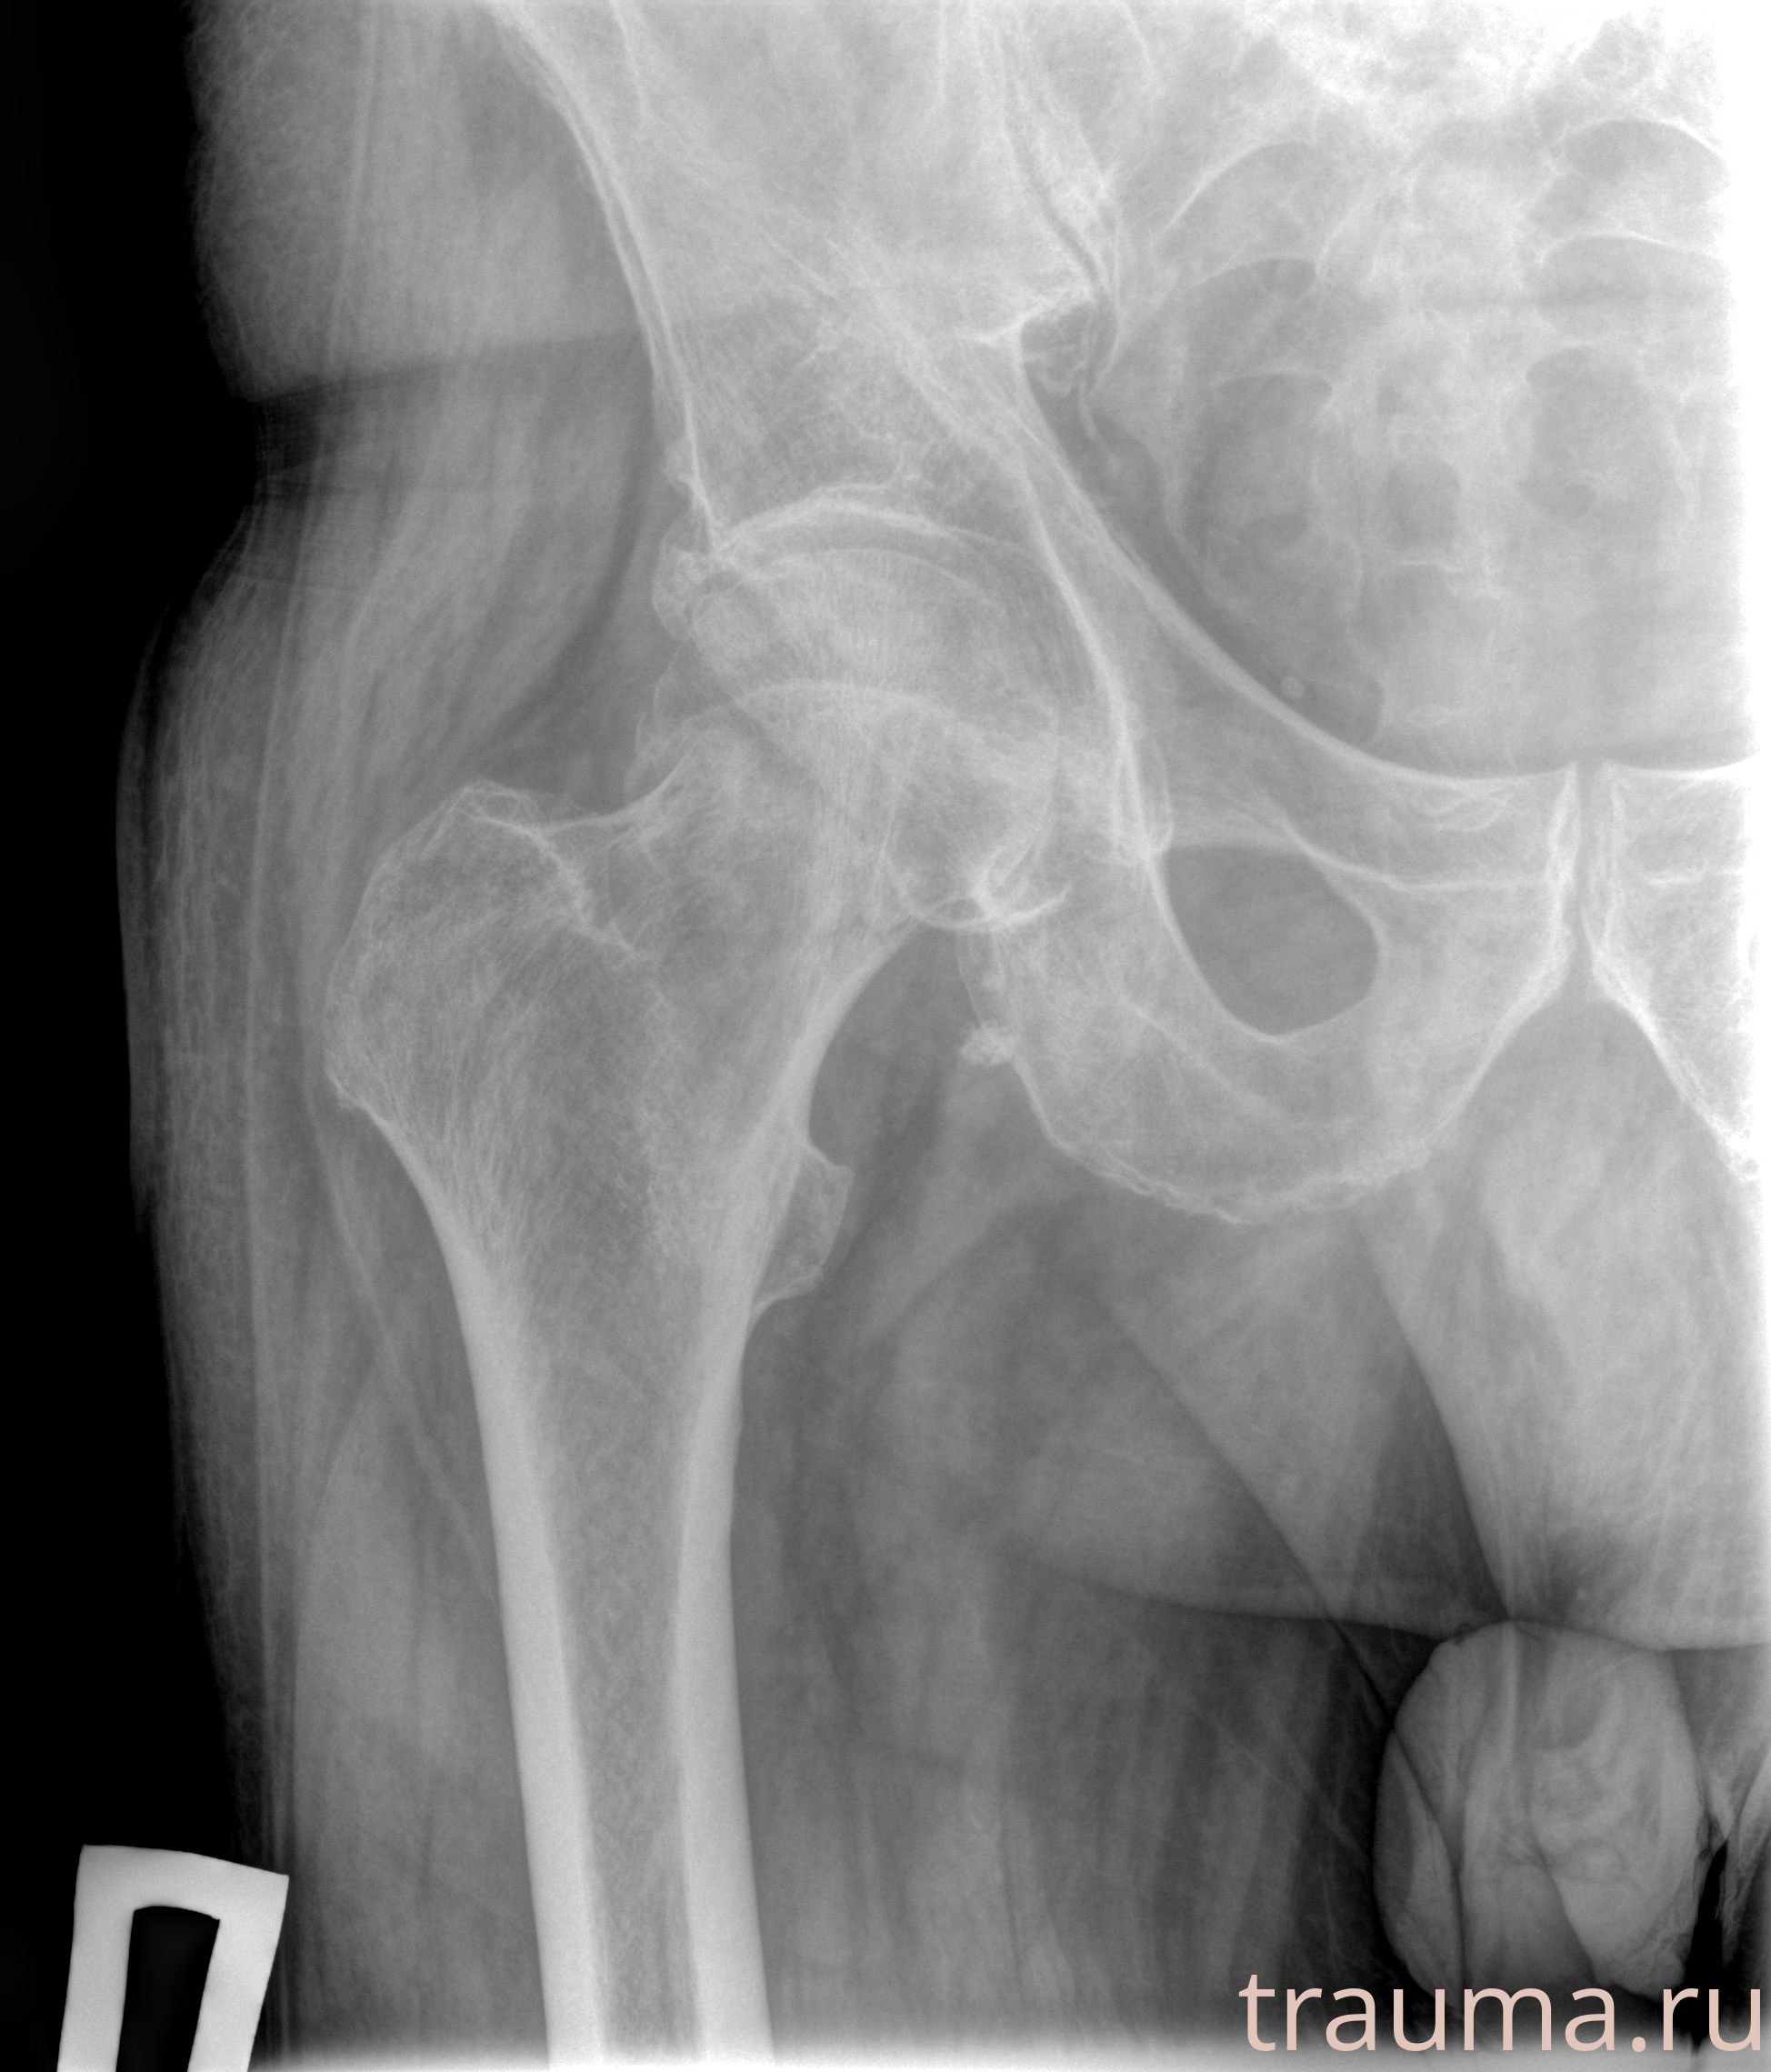

Рентгенограммы

Рентген на дому: по вашему адресу приезжает врач-рентгенолог, травматолог-ортопед с мобильным рентгеновским аппаратом, проводит диагностику травмы или заболевания, делает необходимые рентгенограммы, дает рекомендации по дальнейшему лечению. Получить качественные снимки в домашних условиях возможно благодаря уникальной методике, разработанной МосРентген Центром для института  Склифосовского